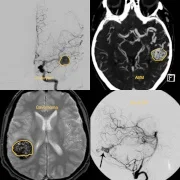

We provide specialized aneurysm and vascular neurosurgery in Thane, offering precise treatment for brain aneurysms, arteriovenous malformations (AVMs), intracranial hemorrhages, and vascular malformations. Using advanced techniques such as microsurgical clipping, endovascular coiling, and bypass surgery, our neurosurgical team ensures life-saving interventions with minimal complications. Our neurovascular specialists in Thane are trained to manage both emergency and elective vascular conditions of the brain with high success rates.